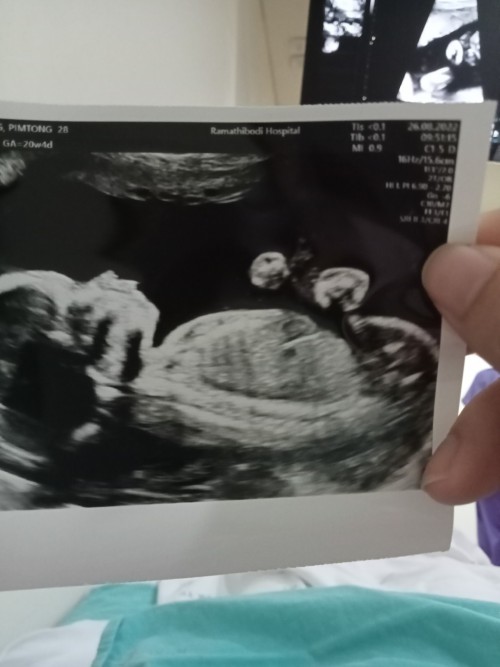

18 ธันวาค่าาา หาหมอรอบหน้าก็รู้เพศแล้ว ตอนนี้17wแล้วค่ะ